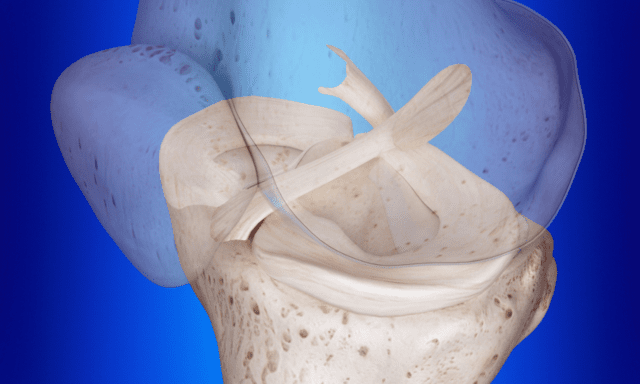

ACL Reha & Biomechanik!

Diesen Monat haben wir den immer wieder fantastischen Enda King zu Gast, um über ACL-Biomechanik und Bewegungsstrategien nach der Operation zu sprechen - ein Gebiet, auf dem Enda seinen Doktortitel gemacht hat! Wir schauen uns an, wie Sie Ihren Patienten objektiv helfen können, auch wenn Sie kein schickes Biomechanik-Labor haben, woher die Idee eines 10%igen Unterschieds für RTP kommt und wie sich das in die Realität überträgt, und wie Sie Ihre Patienten coachen können, ohne durch Bewegungseinschränkungen zu coachen! Einige der Konzepte, über die wir sprechen, ähneln denen, die im Kurs über die drei großen Sehnen behandelt werden! Schalten Sie ein und erfahren Sie mehr!